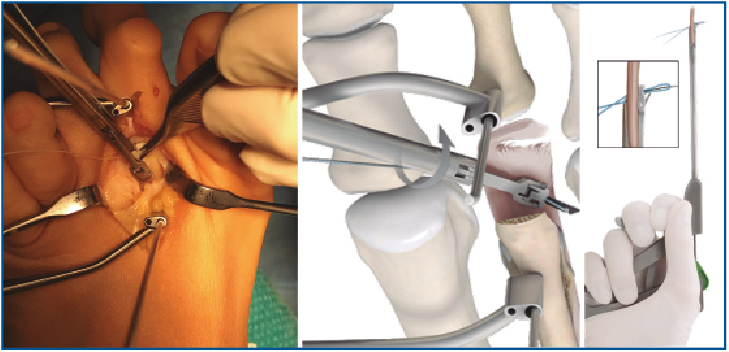

5. Pasamos las suturas por la placa plantar con ayuda de una pinza Mini-Scorpion DX® (Arthrex) (Figura 7) o de un Micro SutureLasso® (Arthrex) (Figura 8). Existen diferentes técnicas según el tipo de rotura. Para la reinserción utilizamos 2 suturas no reabsorbibles de Fiber-Wire® n.º 0 en “doble hilera” proximal y distal (Figura 9). Decidimos una u otra configuración in situ según el tipo de rotura.

Figura 7. Pase de suturas mediante pinza Mini-Scorpion®.

Figura 8. Pase de suturas con ayuda de Micro SutureLasso®.